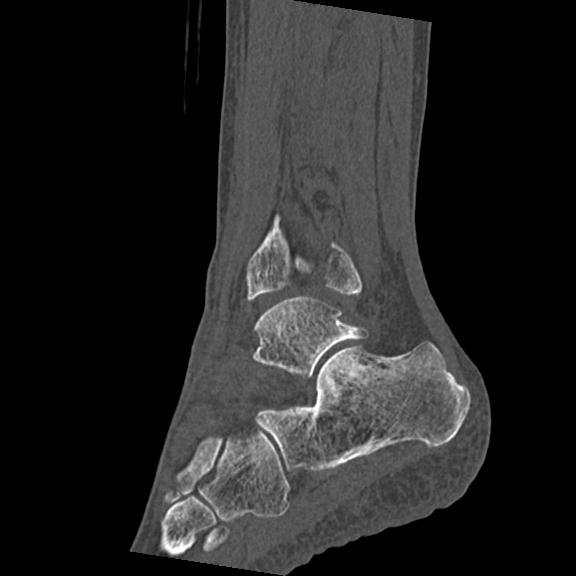

102755 1/4 2R 1/15 2R 右足関節 68歳女性 右三果脱臼骨折